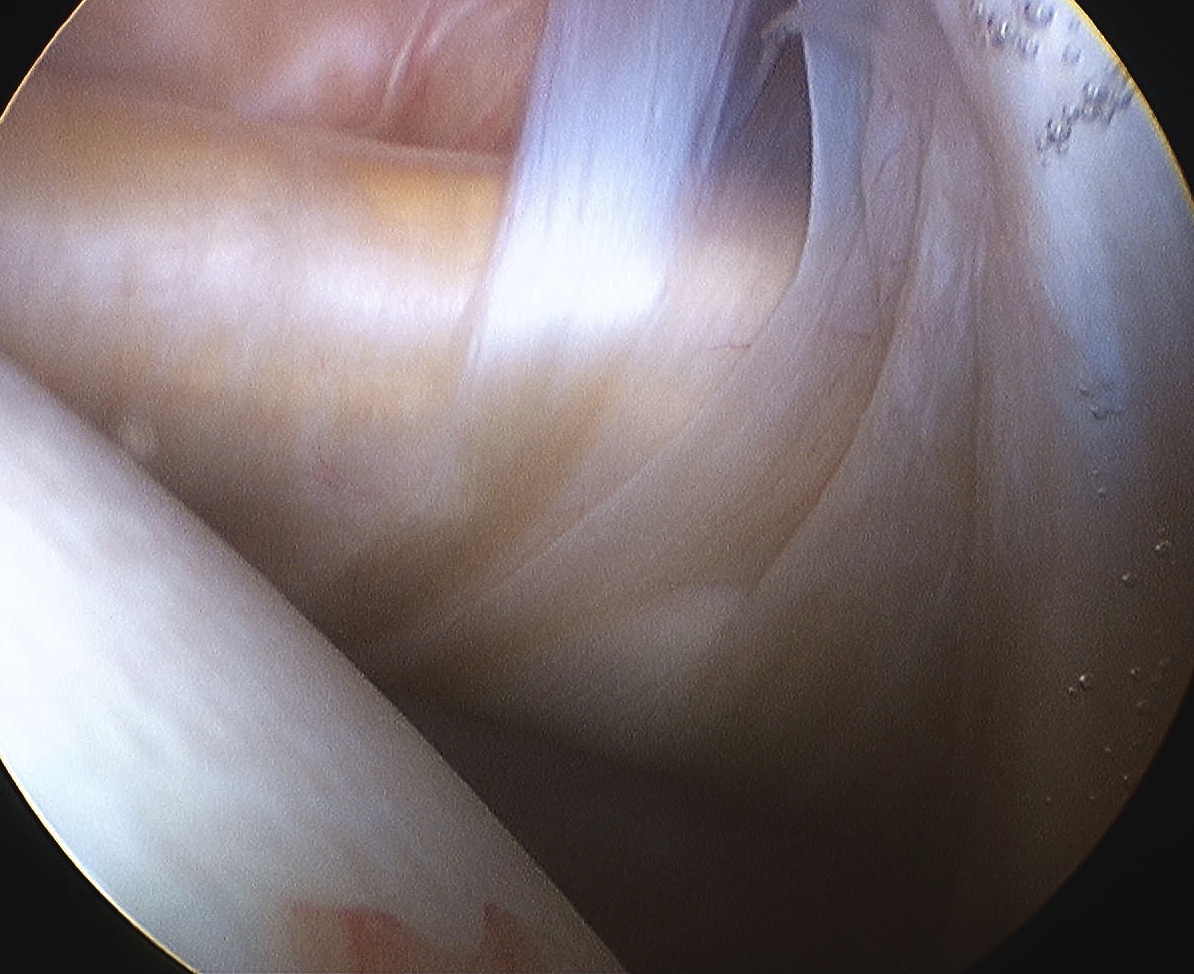

![]() |

Rotator Interval - triangle of glenoid medial, biceps superior, subscapularis inferior

Humeral head cartilage

Glenoid cartilage

Labrum - anterior / inferior / posterior

Biceps tendon / insertion

Subscapularis

Glenohumeral ligaments

Three thickenings of the glenoid capsule: SGHL, MGHL, IGHL